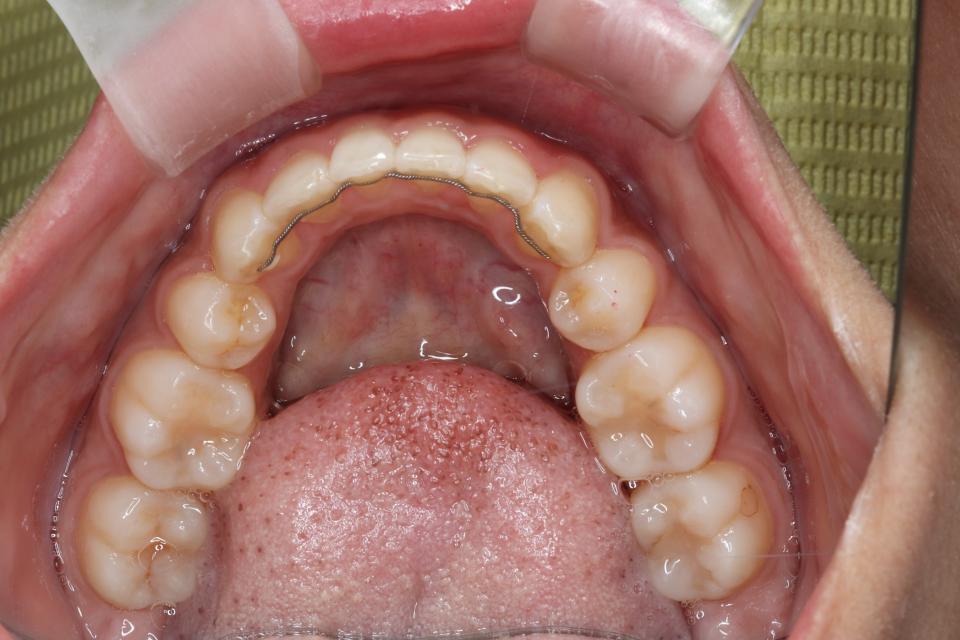

前歯の部分矯正治療(マウスピースによる治療)

マウスピース型の矯正治療装置を使用し、前歯の歯並びのみの改善を行いました。

現在は保定装置を使用し定期的にチェックしています。

| 矯正治療期間 | 12か月 |

| 抜歯の有無 | なし |

| 治療費 | 685,000円 |

歯の移動に伴い痛みを感じる場合があります。 治療後保定装置を使用しないと歯並びが元に戻る可能性があります。 |